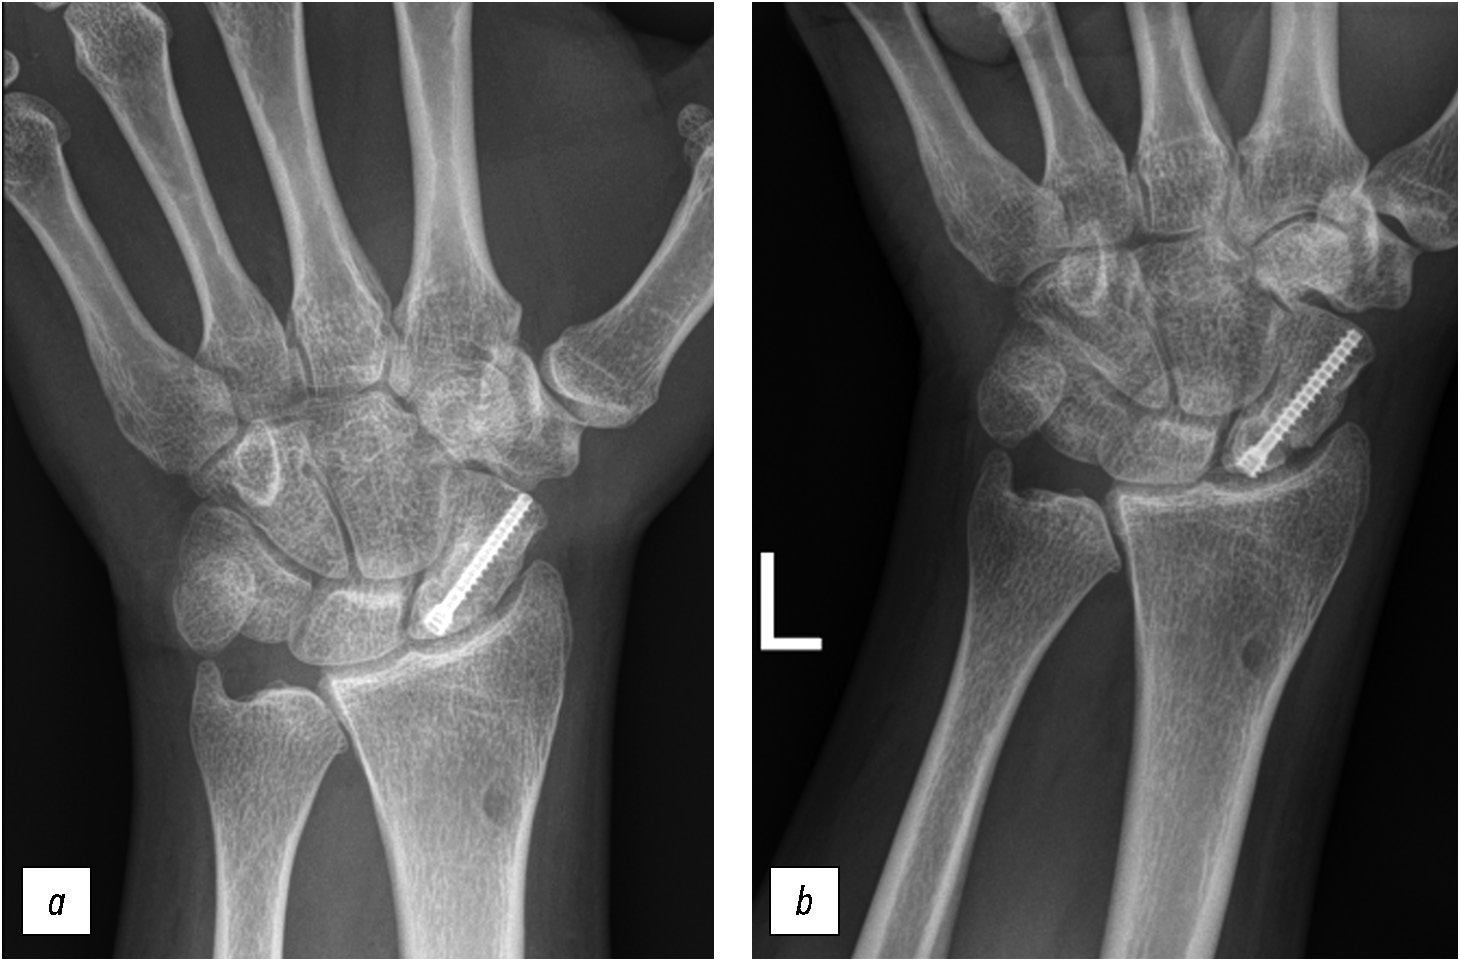

Со времени публикации W.R. Stecher прошло около 90 лет. Оригинальная авторская методика не утратила актуальности и является полезным дополнением к рутинному рентгенологическому исследованию, так как до 20–30% свежих переломов не обнаруживается на стандартных рентгенограммах [3, 4]. Способ Stecher помогает не только в диагностике острой травмы — он полезен и при планировании операции, оценке процесса консолидации перелома или ложного сустава ладьевидной кости на этапах лечения [3]. В отличие от стандартных рентгенограмм данный метод помогает определить истинный размер дефекта кости, степень деформации, состояние суставных поверхностей (рис. 6, 7).

Рис. 7. Рентгенограммы кистевого сустава пациента 34 лет после операции по поводу ложного сустава ладьевидной кости: а — стандартная укладка, достигнута консолидация; b — рентгенография по Stecher, модифицированный вариант (SM): выявлены дефект суставной поверхности ладьевидной кости, начальные признаки деформирующего артроза кистевого сустава.

Fig. 7. Radiographs of the wrist joint of a 34-year-old patient after surgery for a scaphoid nonunion: а — standard position, consolidation achieved; b — Stecher modified radiography (SM): defect of the articular surface of the scaphoid bone, initial signs of arthrosis of the wrist joint were detected.